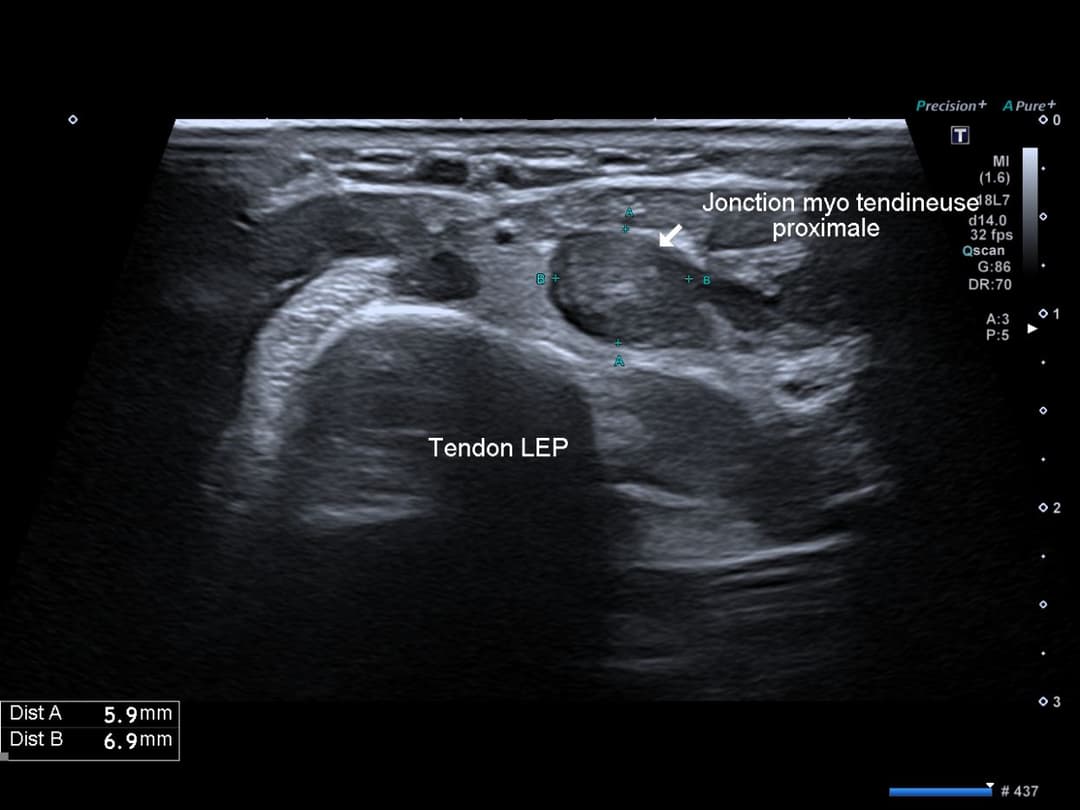

Franc épaississement fusiforme avec désorganisation architecturale du tendon long extenseur du pouce (EPL) actif en Doppler couleur.

Coupe axiale en amont du tubercule de Lister, franc épaississement ovoïde avec désorganisation architecturale du EPL

Hyperhémie en Doppler couleur intra et péri tendineuse